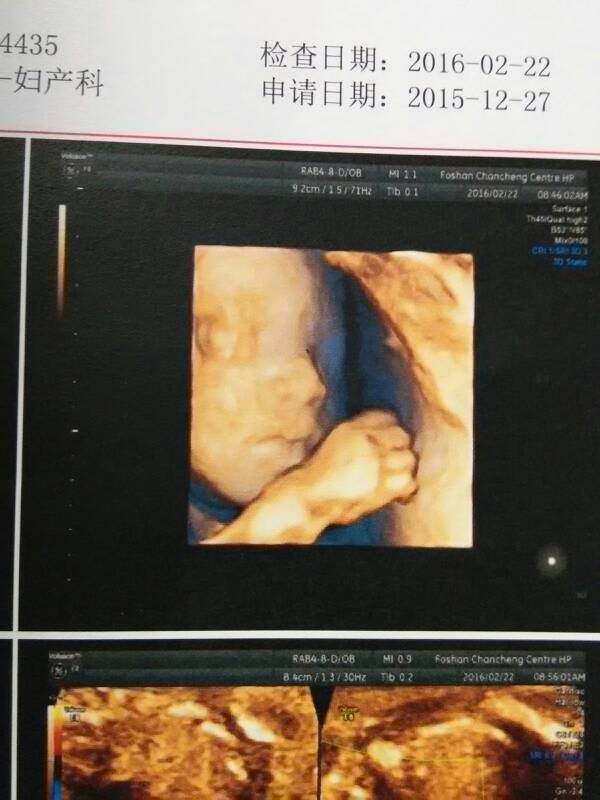

四维照片! 四维照片! 点击展开 186*****608_EFzi 2019-11-09 21:13 为您推荐: 其他回答 祝你家宝宝健康漂亮 我姓周我心绉i 2020-03-02 12:42 好可爱的宝宝 156*****353_RpBp 2020-03-01 06:50 好可爱的宝宝 诺小c 2020-02-28 06:30 恭喜恭喜,很高兴吧 幸运的昕洋 2020-02-19 06:27 好可爱。。 萌宝贝瑶瑶 2020-02-13 12:38 加载更多 相关问题 做四维医生给老公看照片吗 六个月做四维照片和以后生下来小孩长一样吗 怀孕25周四维照片显示孩子的嘴那多了一块不知道是什么,医生